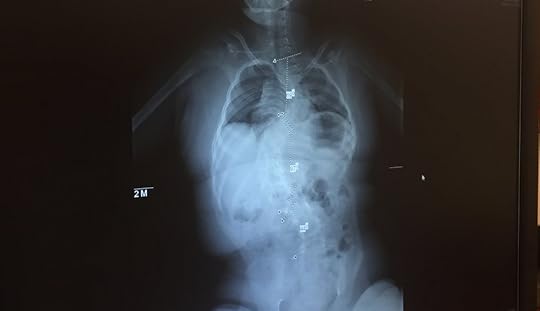

The x-ray was her favorite part and because she loved it so much, it was also THE highlight to my day. “Up, up and away”, I’m sure she thought as she sat with excitement and anticipation as if she were loading onto a ride at Disney World.

Unfortunately, the scans didn’t look good— one might say they even looked quite bad. Anyone could see without a medical degree that her curve had increased to 100% and was encroaching on her lungs and heart. Not a candidate for surgery, our only step is to wait and see the next scan in nine months and to visit a pulmonologist as soon as possible.

Scoliosis isn’t an uncommon diagnosis with Avery’s rare chromosome disorder and she has lived with it for quite some time. What is surprising, however, is how well she is physically hiding a curve as significant as hers and that she remains able to sit upright and maintain a great balance. While often operable, Avery’s physical condition from her chromosome disorder leaves her in a holding pattern until she is large enough to benefit from the very invasive, extensive and often just one of many surgeries to attempt to slow or fix a condition of scoliosis as bad as hers.